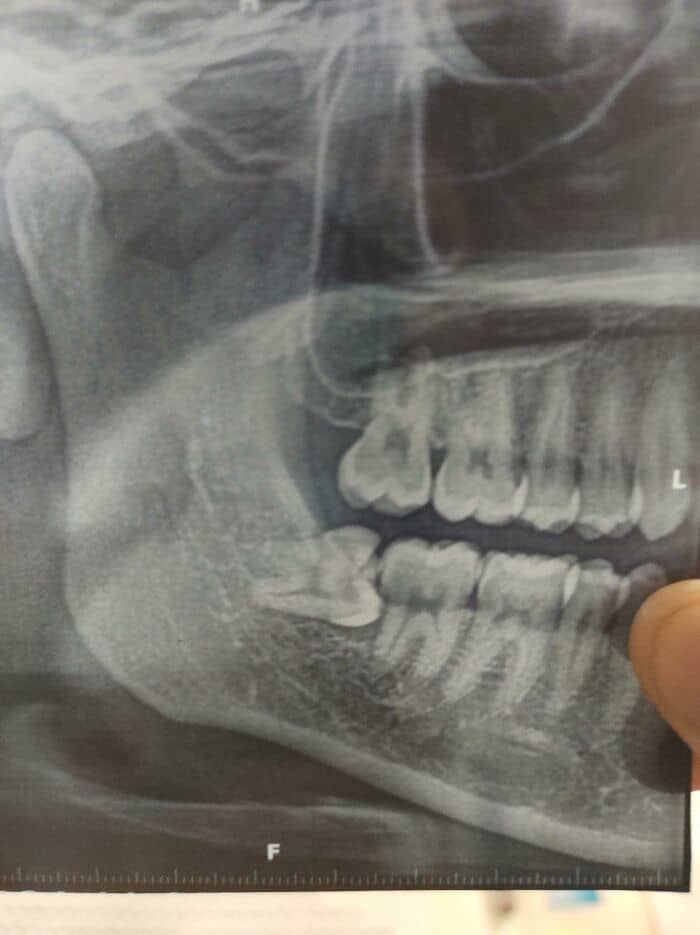

#54 Two Of My Wisdom Teeth. They Were Completely Sideways